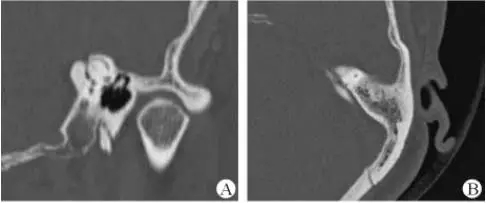

診斷及治療

醫生若懷疑此病將會安排內耳CT掃描。在大多數案例中,一旦此病被耳鼻喉科醫生或其它聽力健康專家確診,則可實行手術治療。外科手術風險包含聽力損失以及神經損傷;重建及復原需內耳的治療以及大腦的重塑。